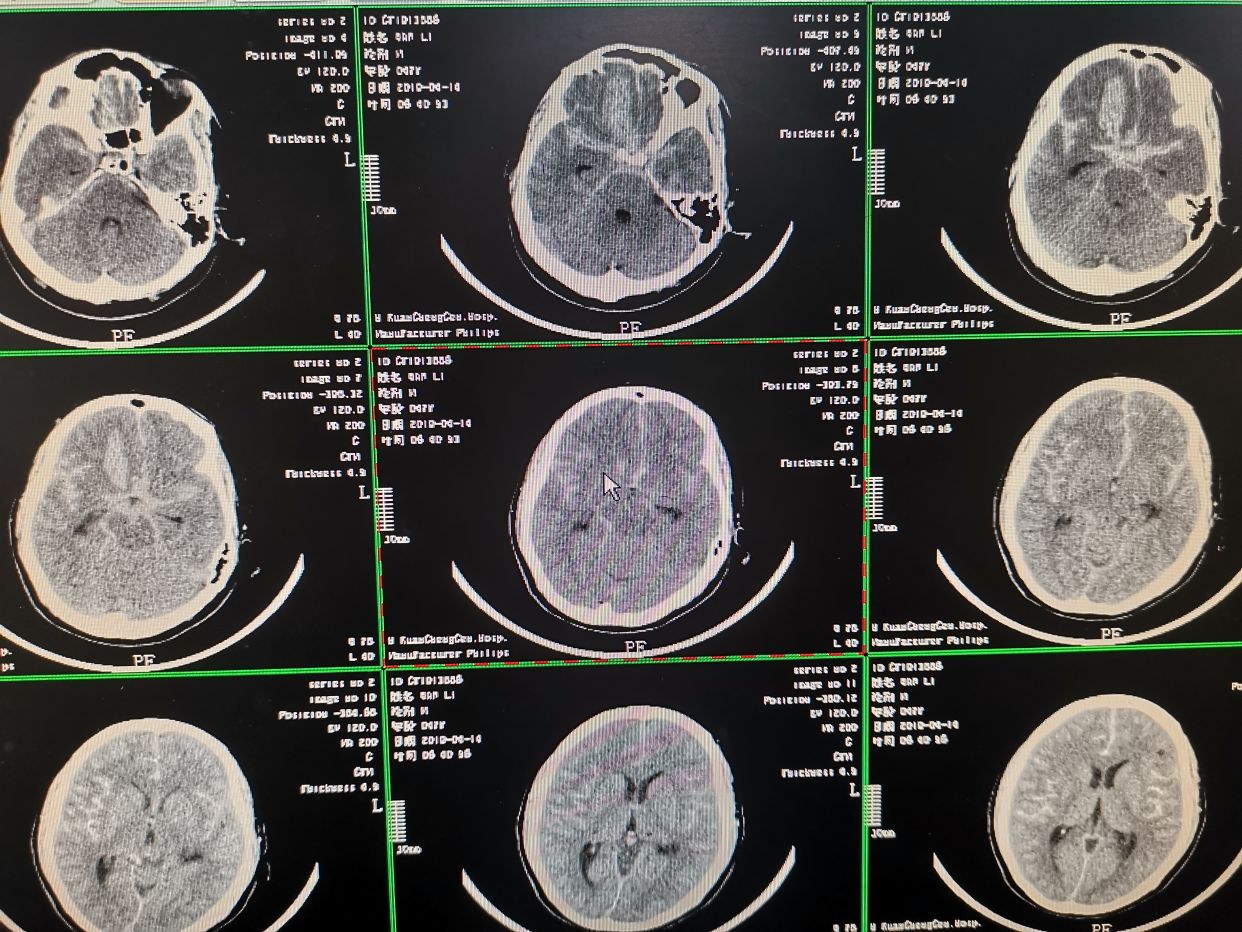

入院CT提示蛛网膜下出血,右额叶出血。

入院CT检查

造影结束。患者全麻状态,观察患者瞳孔,右侧瞳孔散大,对光反射消失。立即行CT检查发现右额叶脑内血肿较前明显增加,脑内血肿形成。相关病情告知家属。拟立即快速行弹簧圈填塞术,术后直接入手术室行右侧开颅脑内血肿清楚术+去骨瓣减压术。

术后即刻CT。术后给予对症支持治疗。

术后第八天CT